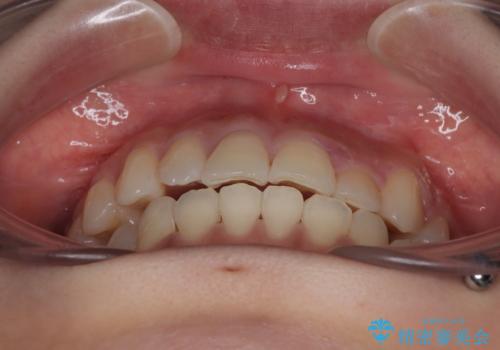

- 左上の前歯のがたつきを主訴に来院された患者様です。

上顎歯列が下顎の歯列に対して狭小であり、一部下顎の奥歯が上顎よりも外側に位置している状態でした。

上顎の歯列を拡大しスペースを設け、さらに左上の小臼歯を一本抜歯し左上の八重歯を歯列内に入れ整えていくことにしました。